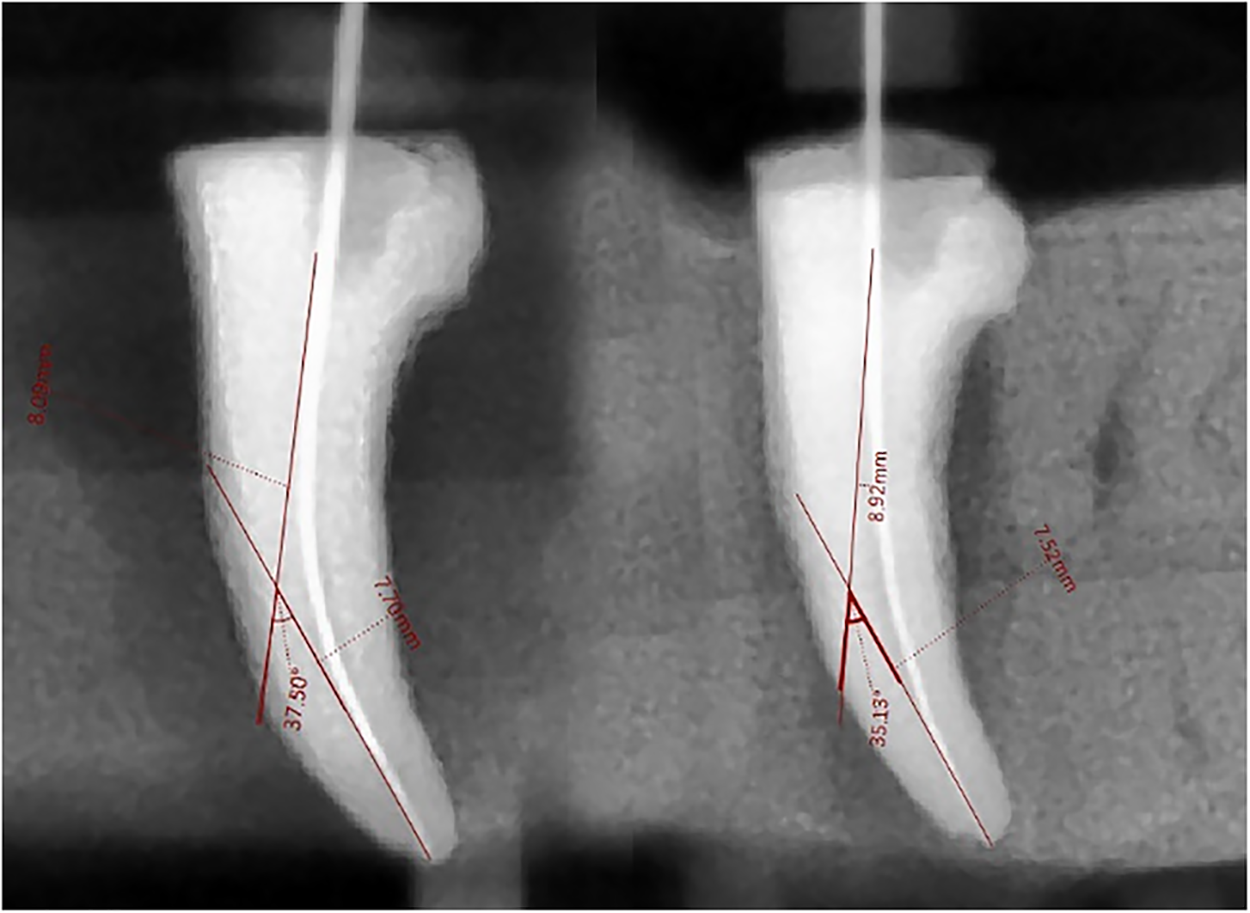

Lastly, sterile paper tips were used to dry the canals. Only the researcher prepared each channel. The following instrumentation, the same circumstances as for initials were used for the specimens to take radiographs using digital dental periapical imaging (Figs. 1–3). The identical method as previously described was used to take the post-operative photos. The same procedure was used to measure the specimens’ canal curvatures. The initial measurement was of the post-instrument canal curvature.

Fig. 2. Pre- and post-instrument curvature change in group B.